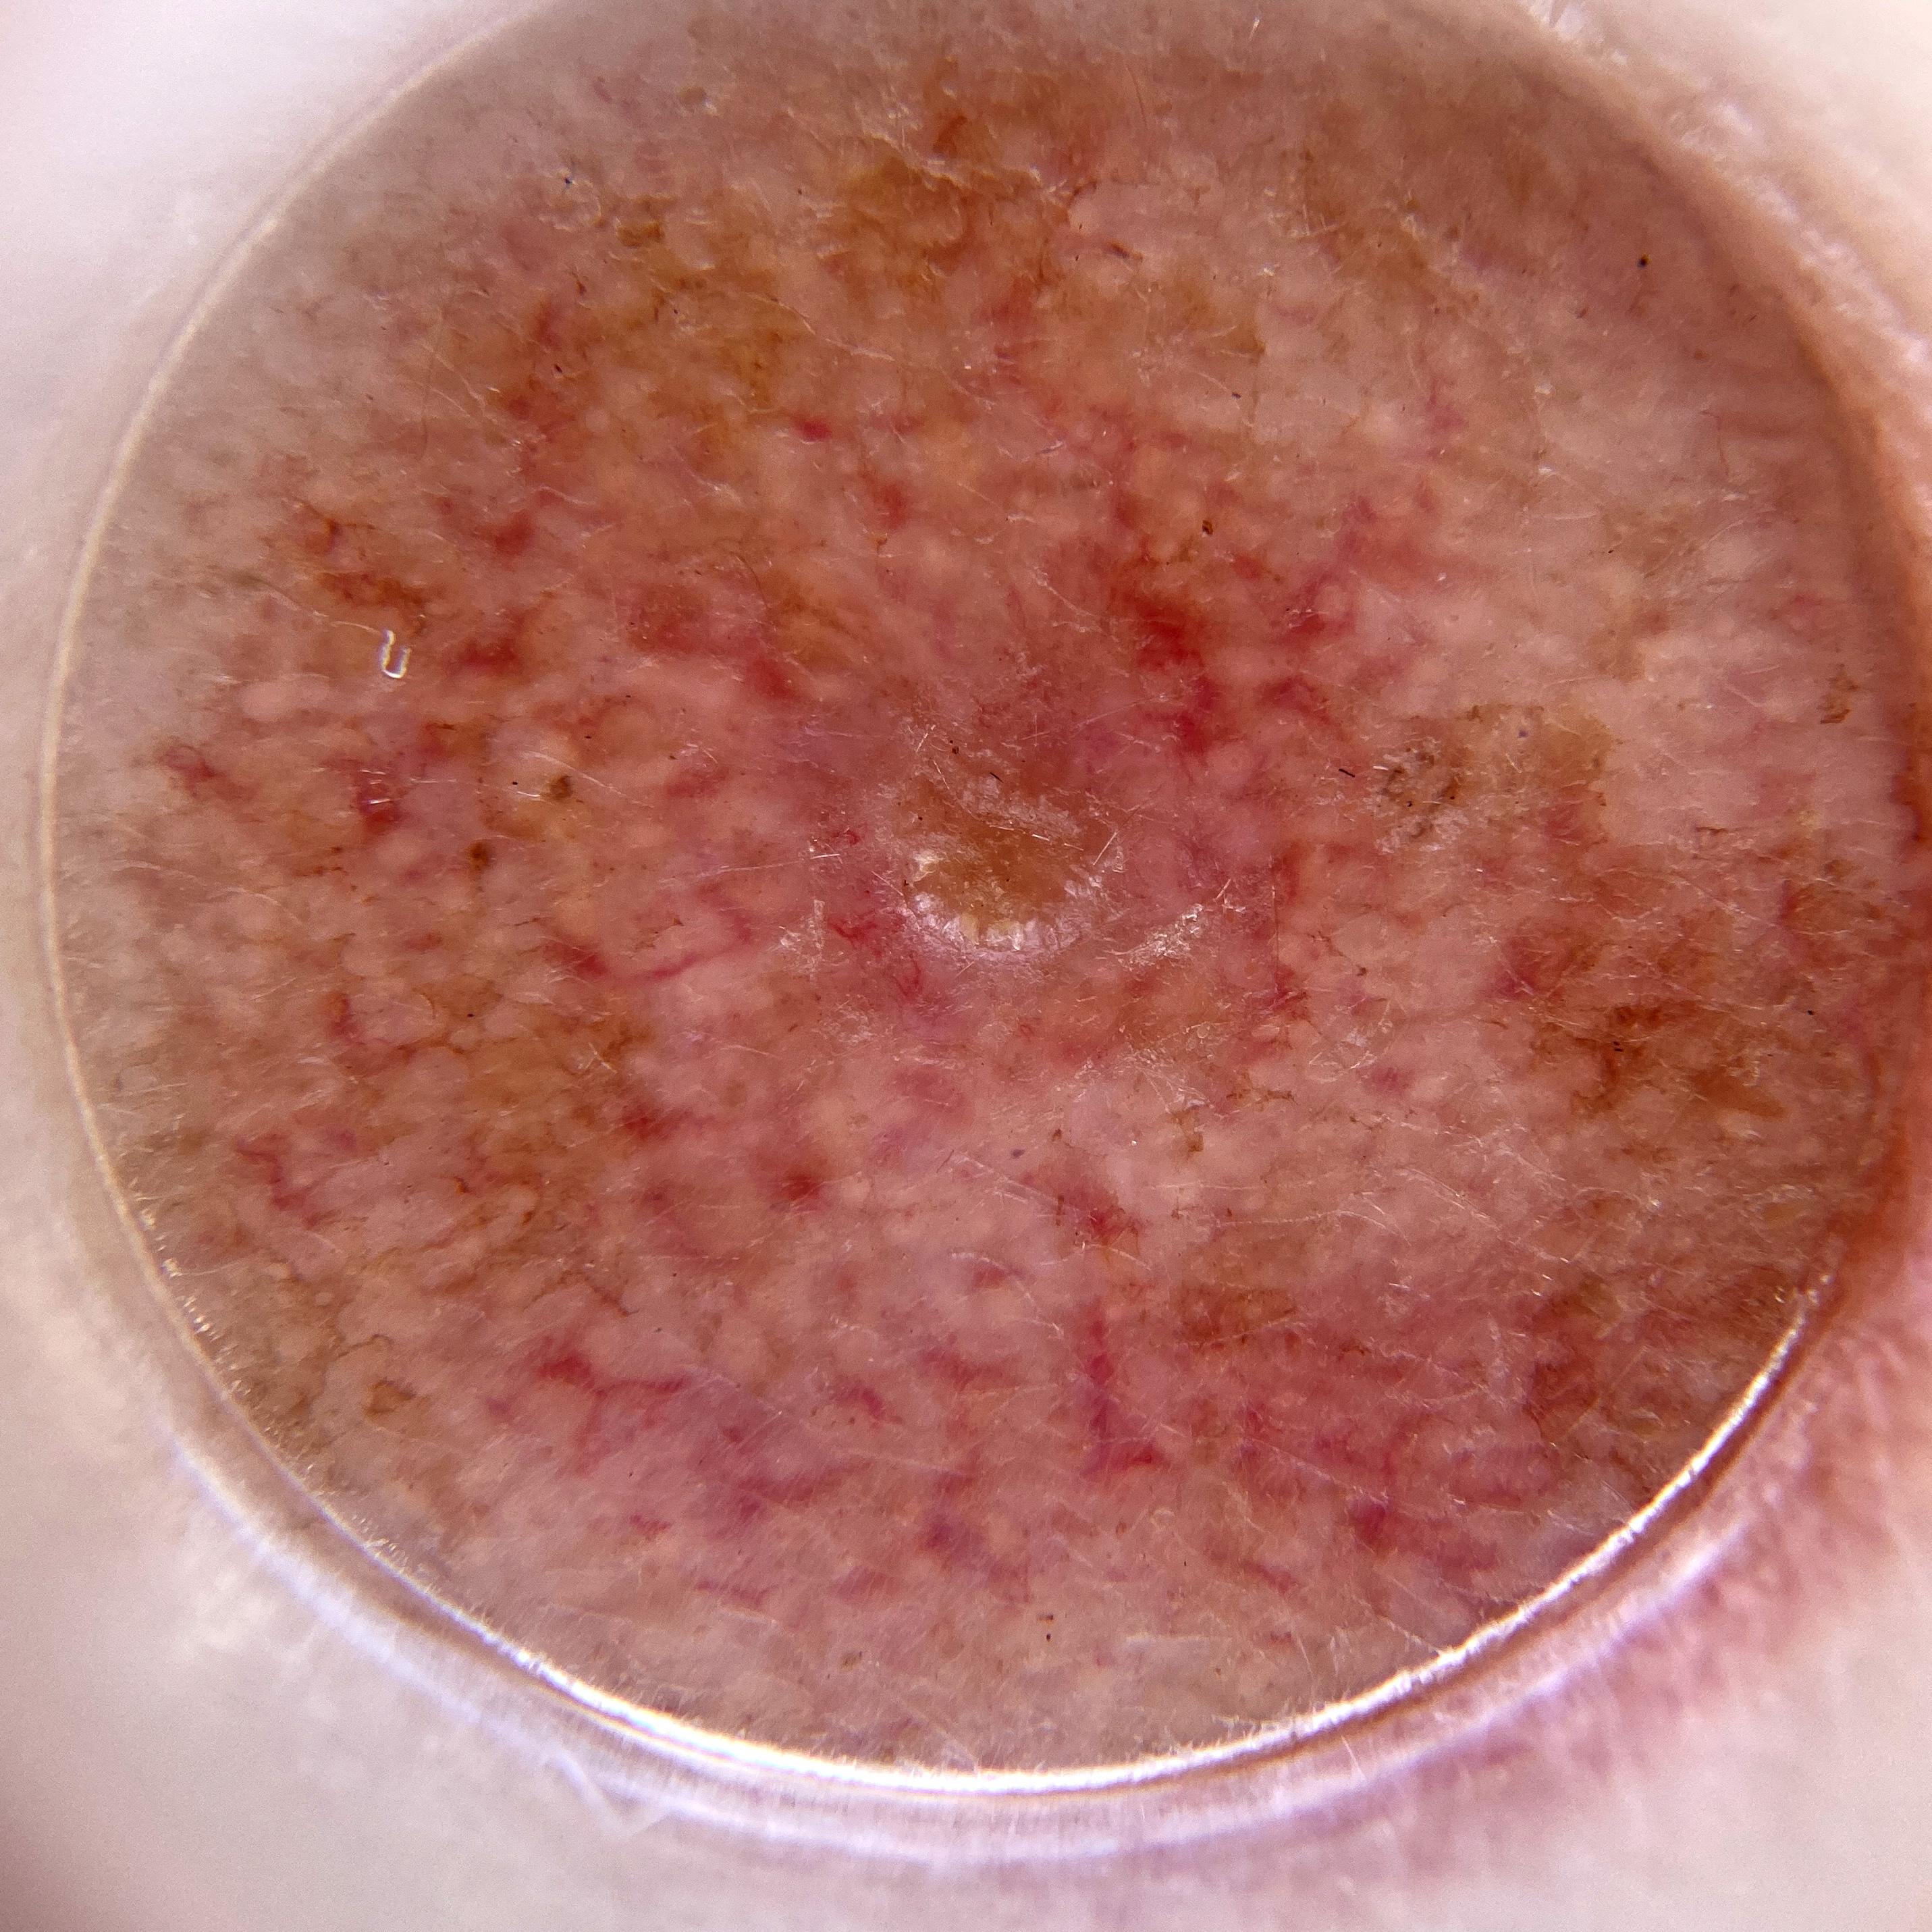

ISIC_7519464

IP_3612490

IL_7662406

Clinical

Field Value

acquisition_day 84

age_approx 70

anatom_site_1 Head and neck

anatom_site_general head/neck

diagnosis_1 Benign

family_hx_mm True

fitzpatrick_skin_type I

image_manipulation instrument only

image_type dermoscopic

lesion_id IL_7662406

patient_id IP_3612490

personal_hx_mm True

sex male